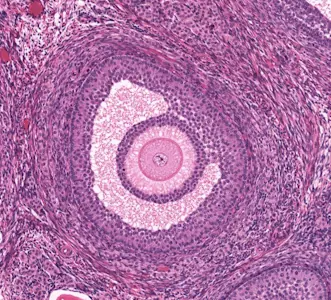

Transvajinal ultrasonografi, vajina yoluyla yapılan bir ultrason incelemesidir. Bu teknik, abdominal (karın üzerinden) ultrasona göre daha net görüntüler sağlar çünkü ultrason probu yumurtalıklara daha yakındır. TVUSG, over rezervini değerlendirmek için ideal bir araçtır çünkü antral folikülleri (küçük, dinlenme halindeki yumurta kesecikleri) doğrudan görselleştirebilir. Bu foliküller, yumurtalıkların içindeki 2-9 mm çapındaki sıvı dolu yapılarıdır ve rezervin bir göstergesidir.

Antral folikül sayımı, yumurtalıklardaki antral foliküllerin sayısını belirleme işlemidir. Bu foliküller, yumurtalık rezervinin bir yansımasıdır çünkü her ay bir grup folikül olgunlaşmaya başlar ve geri kalanı atılır. AFC, over rezervinin azaldığını erken tespit etmek için kullanılır. Düşük AFC, yumurtalıkların stimülasyona (örneğin tüp bebek tedavilerinde ilaçlarla) zayıf yanıt vereceğini işaret edebilir.

AFC, doğrudan over rezervini temsil eder çünkü antral foliküller, gonadotropin hormonlarına duyarlıdır ve yumurta üretim potansiyelini gösterir. Bir inceleme, AFC’nin over rezervini değerlendirmede altın standart haline geldiğini vurgulamıştır. Diğer testlerle (örneğin AMH hormonu seviyesi veya FSH testi) kombine edildiğinde daha kapsamlı bir resim çizer.

- Görüntüleme: Prob, yumurtalıkları tarar. Her yumurtalığın kesitleri alınır ve antral foliküller (2-9 mm çapında, yuvarlak, sıvı dolu yapılar) sayılır. Sayım, her iki yumurtalık için ayrı ayrı yapılır ve toplam AFC hesaplanır. Örneğin, sağ yumurtalıkta 5, solda 6 folikül varsa toplam AFC 11’dir.